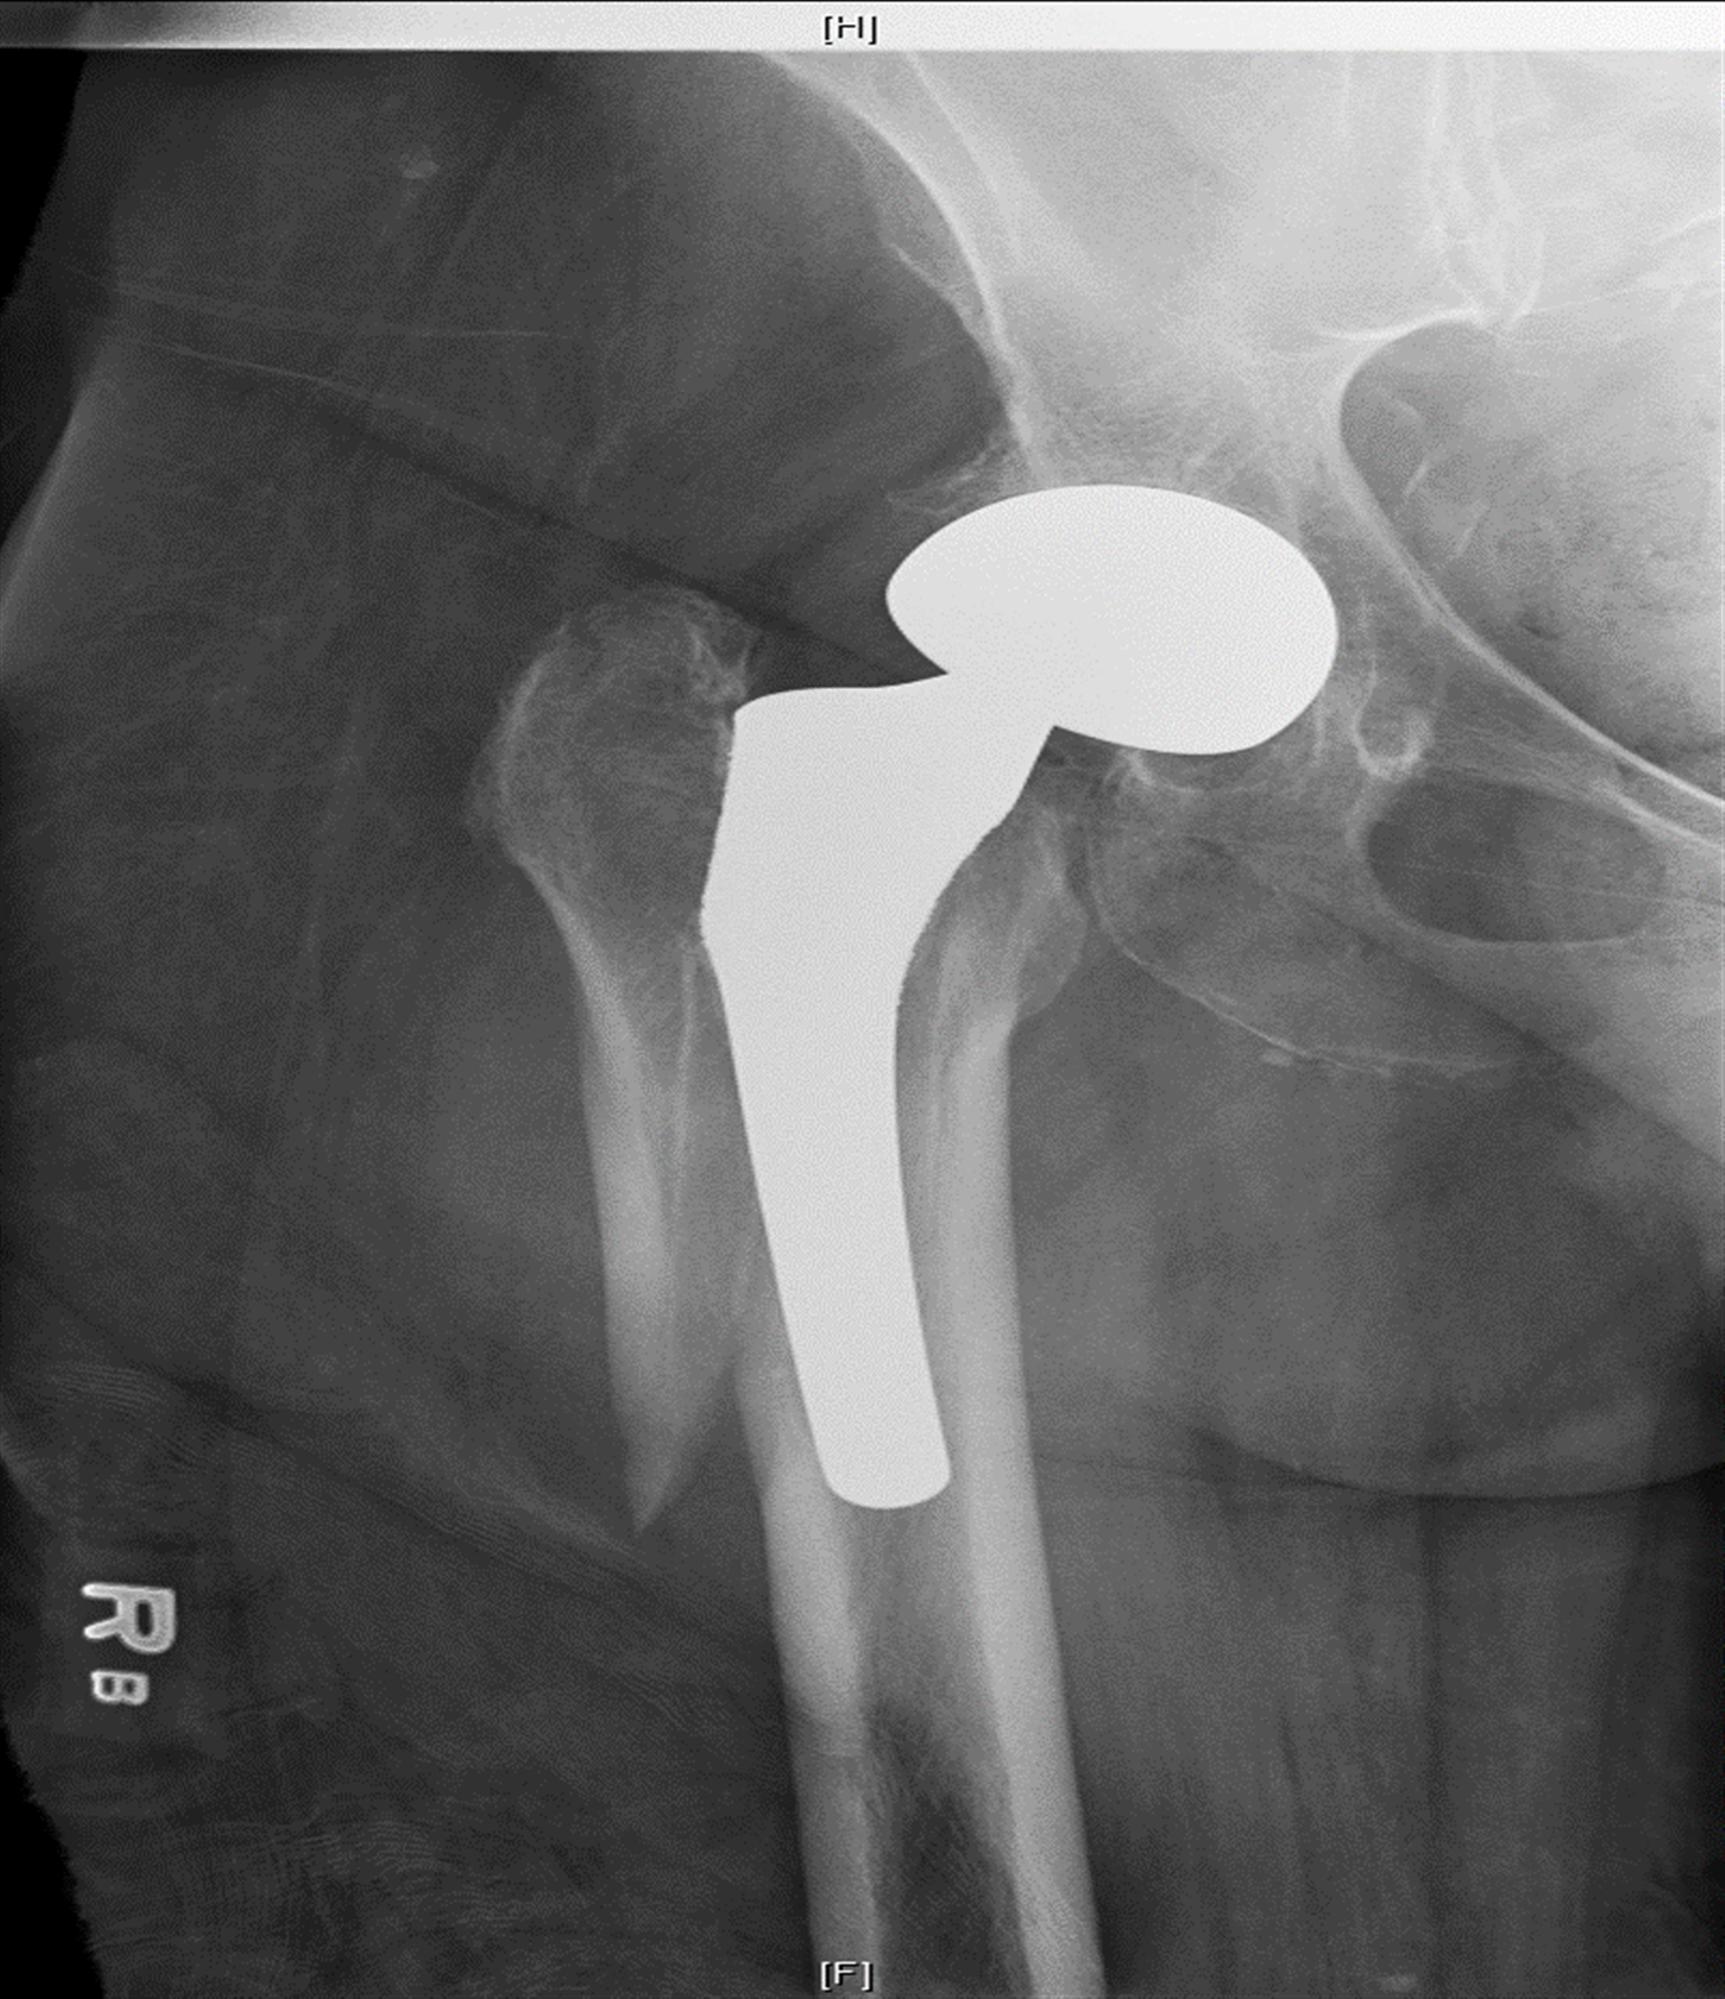

일상생활을 하다가 부러진 경우에도 똑같은 Vancouver Classification 을 사용합니다. 수술중과 큰 차이는 위치에 따라 골절을 나뉘고 B만 구체적으로 나누고 나머지는 그냥 A,C로 골절을 나뉩니다. STEM 이 헐거운 경우 B2, STEM 바로 아래는 B1, 삽입물 주변의 골절 또는 뼈가 부족한경우 B3로 이해하면 됩니다.